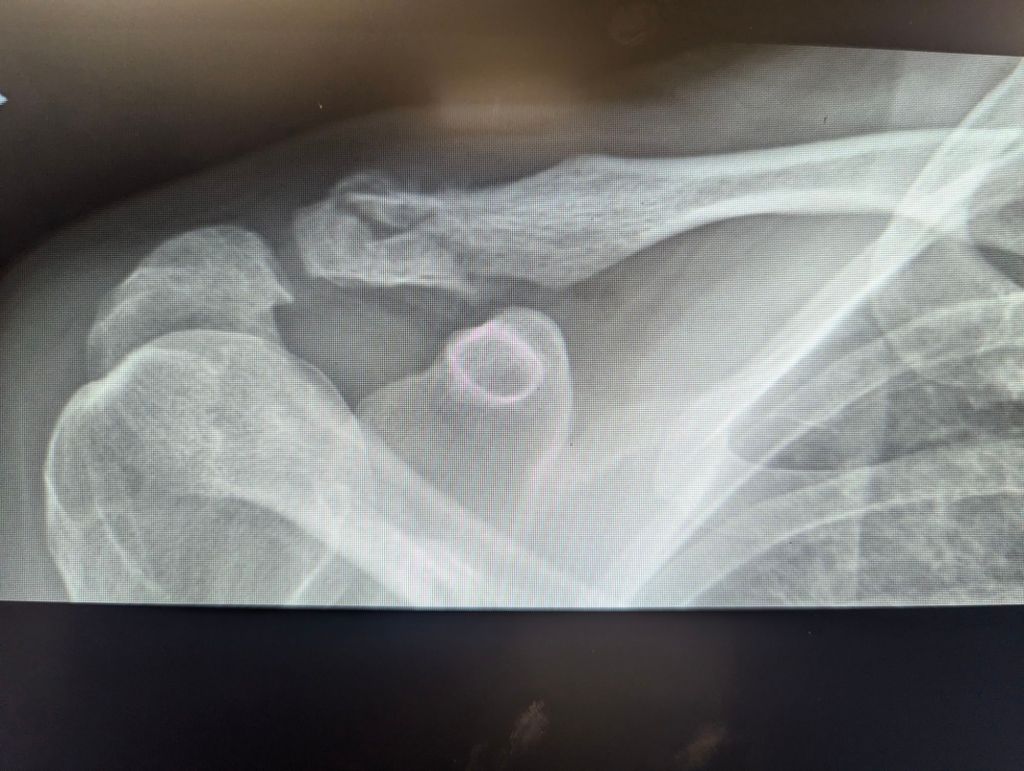

walking with Artie on a morning when the temperature hovers around zero; hours before the thermometer will plummet. the last drops fall just before they freeze. yesterday, Mikayla was awarded for simply being who she is. the embodiment of kindness. like her Mom. like her Gramma. my recent clavicle image tells me the regular activity I began two weeks ago was okay to begin 😜